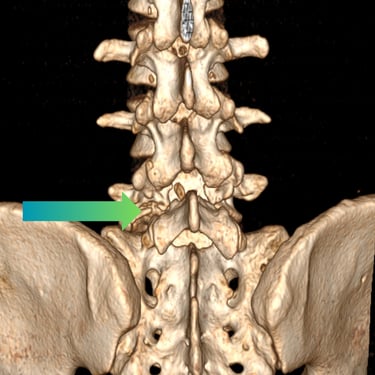

Listesis Lumbar L5–S1 por Fractura Ístmica: Estabilización con FTP y TLIF

La listesis lumbar L5–S1 por fractura ístmica se produce por un defecto en la pars interarticularis que genera inestabilidad vertebral, dolor lumbar crónico y compromiso radicular. Cuando el tratamiento conservador no es efectivo, la artrodesis lumbar con fijación transpedicular (FTP) asociada a la fusión intersomática transforaminal (TLIF) es una alternativa quirúrgica eficaz. Este procedimiento permite descomprimir las raíces nerviosas, restaurar la alineación vertebral y lograr una fijación sólida del segmento afectado. La combinación de estabilización y fusión reduce el dolor, mejora la función y favorece una recuperación segura y progresiva.